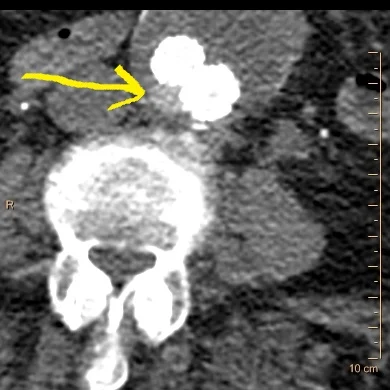

Conventional CT with focal hyperdensity adjacent to endograft